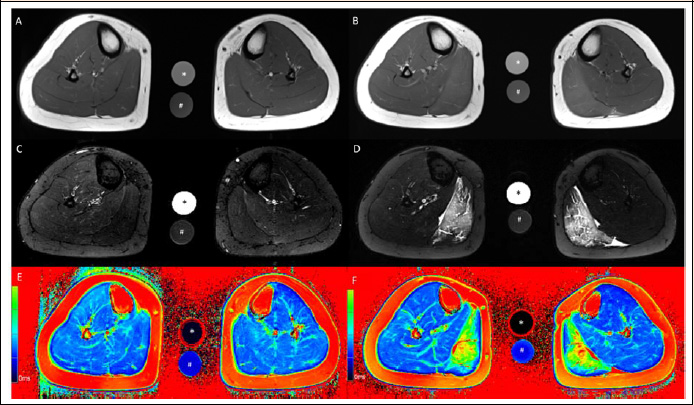

Figure 3.

Axial T1-weighted (A, B), axial T2-weighted TIRM (C, D) and axial T2 mapping (E, F) images of the lower leg at baseline (A, C, E) and 60 h after standardized eccentric exercise of the calf muscles (B, D, F). Muscle edema is apparent in the medial gastrocnemius muscle in the post-exercise images (B, D, F). This participant wore the compression sock on the left calf for 60 h after eccentric exercise. The calibration tubes contain 40 mmol/L NaCl (*) and 40 mmol/L NaCl 5% agarose (#).